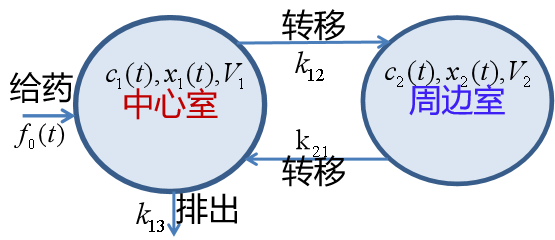

图14 详细的二房室模型

【建立模型】

根据假设和图14所反映的关系,有如下模型 【4.1】